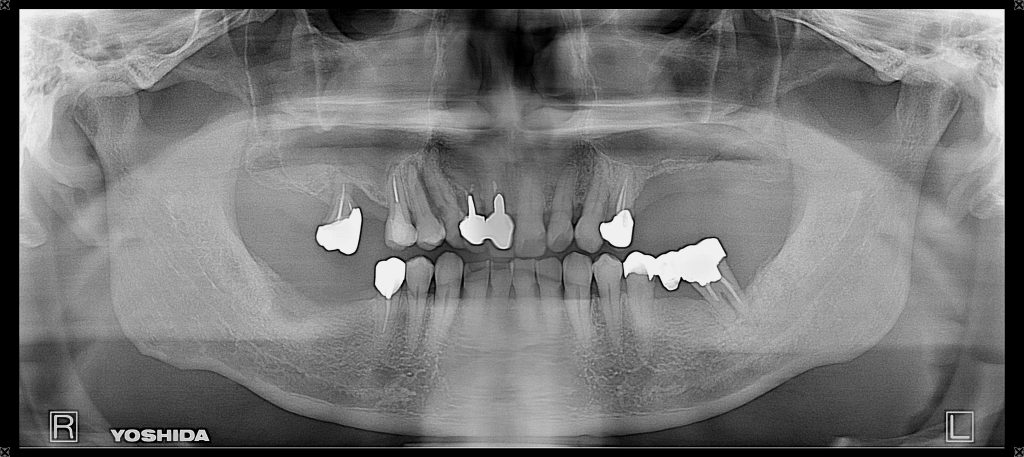

症例360代 男性 奥歯で噛めない 昔、義歯を作製したが煩わしく入れていない

治療前

治療後

治療前

治療後

治療前

治療後

治療前

治療後

左右大臼歯部は、残存骨が1~2㎜程度であったが、共にソケットリフト(上顎洞洞底膜挙上術)を行いインプラントを埋入。

約5ヶ月間の治療期間を経て、全てジルコニアを装着し終了。

リスクとしては外科的侵襲がある。デメリットは、保険外診療の為、経済的負担がある。

費用 187万(税込)(オペ・仮歯・最終補綴物まで含む)